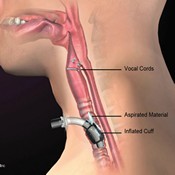

A significant amount of literature has been published providing evidence that a multidisciplinary team approach is critical to the care of patients with tracheostomy. Tracheostomy teams are essential to earlier and more consistent use of the Passy Muir® Valve as a critical intervention for communication, swallowing, rehabilitation, and decannulation, which results in reduced total tracheostomy time, length of stay, adverse events, and cost of care.

Develop a facility-wide program for all tracheostomy and mechanically ventilated patients to be evaluated for candidacy for the Passy Muir Valve within 24 hours of admission, and at appropriate times throughout their stay.

- Incorporate the Passy Muir Valve into ventilator weaning and decannulation policies and procedures.